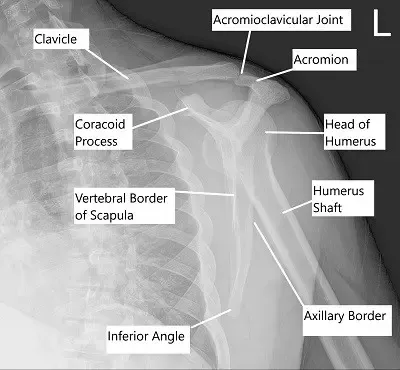

Vista transescapular del hombro izquierdo.